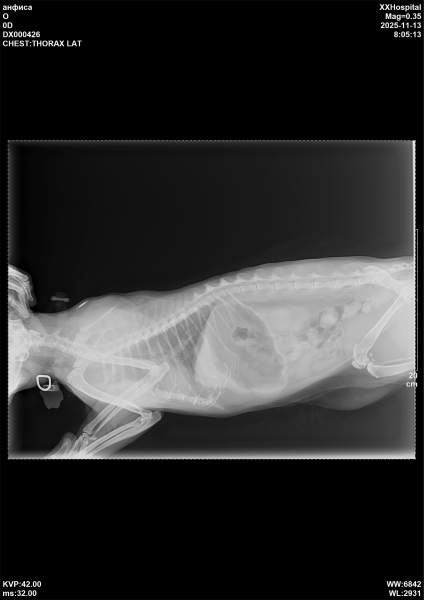

Просим помощи на возрастную кошечку.

Эта киса чистая по пцр влк и вик

Но носитель как и все герпесвируса и корнавируса.

Сейчас обострение, развилась бронхопневмония.

Сейчас задача начать антибиотикотерапию. Может и 2 курса

Оплатили срочно в круглосутке- вышло 7 тр

Сдали биохимию и ОАК. По ОАК воспаление. Сделали рентген- в 2 часа ночи и в 8 утра

Бронхопневмония и заложенность носика сильная.